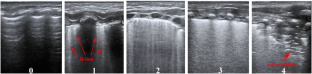

This was a single-center prospective observational study. Preterm infants with a gestational age ≤ 25 weeks were included. Two LUS score protocols were evaluated on the 14th day of life (DOL): (A) evaluating the anterolateral (LUS score-al) lung and (B) the anterolateral combined with posterior (LUS score-alp) lung. The LUS score range for the two protocols was 0–32 and 0–48, respectively.

A total of eighty-nine infants were enrolled. Both the LUS score-al and LUS score-alp were higher in neonates developing BPD and msBPD than in the rest of the cohort (LUS score-al 24 (23,26) vs 22 (20,23); LUS score-alp 36 (34,39) vs 28 (25,32)) (LUS score-al 25 (24,26) vs 23 (21,24); LUS score-alp 40 (39,40) vs 34 (28,36)). The LUS score-al on the 14th DOL showed a moderate diagnostic accuracy to predict BPD and msBPD (AUC 95% CI: 0.797 [0.697–0.896]; 0.811[0.713–0.909]), while the LUS score-alp significantly improved diagnostic accuracy of BPD and msBPD (AUC 95% CI: 0.902 [0.834–0.970]; 0.922 [0.848–0.996]). A cutoff of 25 points in the LUS score-al provided a sensitivity, specificity, positive likelihood ratio, and negative likelihood ratio of 76.9%, 79.4%, 3.7, and 0.3 respectively to predict msBPD. Meanwhile, that of 39 points in the LUS score-alp provided a sensitivity, specificity, positive likelihood ratio, and negative likelihood ratio of 81%, 98.4%, 50.5 and 0.19 to predict msBPD, respectively.